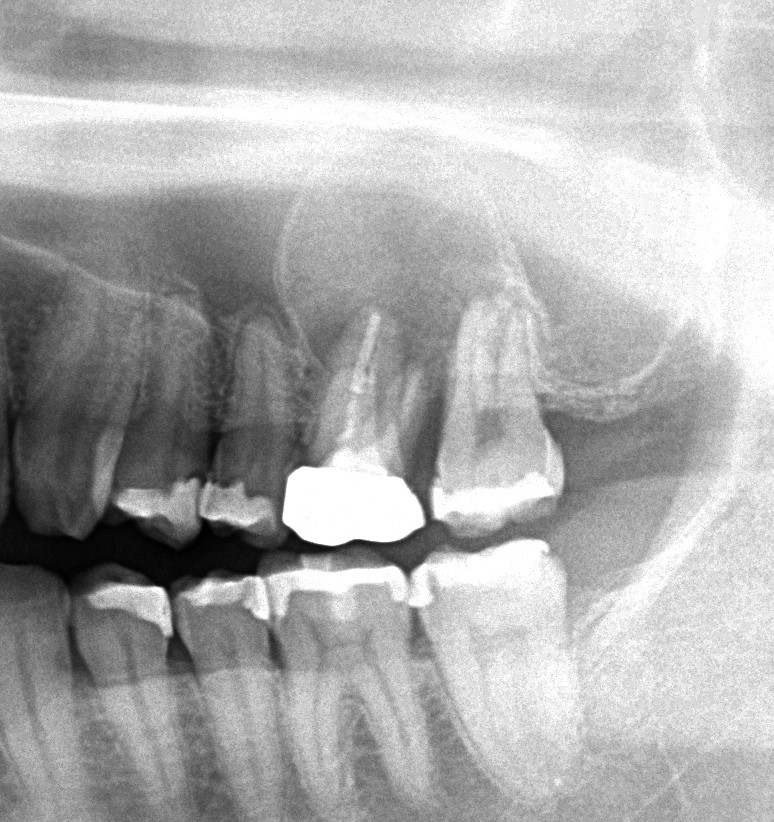

この写真の方は左上が噛むと痛いとして来院された患者様です。

パノラマでは上顎洞に広がる歯根嚢胞が認められます。

この方の場合は歯が歯周病でぐらついているのもあるので、歯を抜歯して外科的にすべて取り除く方法でやっていくことになりました。